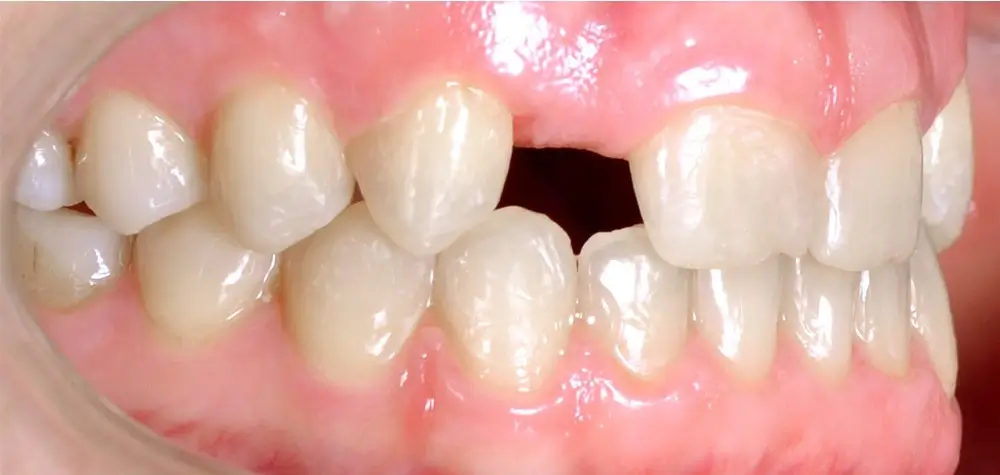

Кейс 8

Количество кап ВЧ 24

Количество кап НЧ 24

ДО